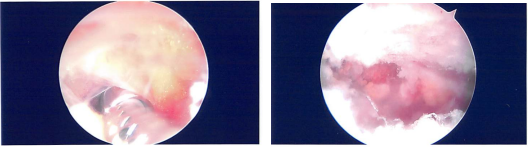

Lateral entry portal was made and the scope entered. There was ____ In the patella as well as on the medial femoral condyle which after making a medial portal, cleaned arthroscopically using a shaver.

Examination of the medial meniscus showed a tear of the anterior horn of the medial meniscus which was clean. The intercondylar notch showed an intact ACL. Lateral tibiofemoral compartment examination was normal.

After thorough Irrigation, final pictures were saved and the wound was closed. Then, 40 mg of Depo-Medrol was injected in the left knee after the surgery.